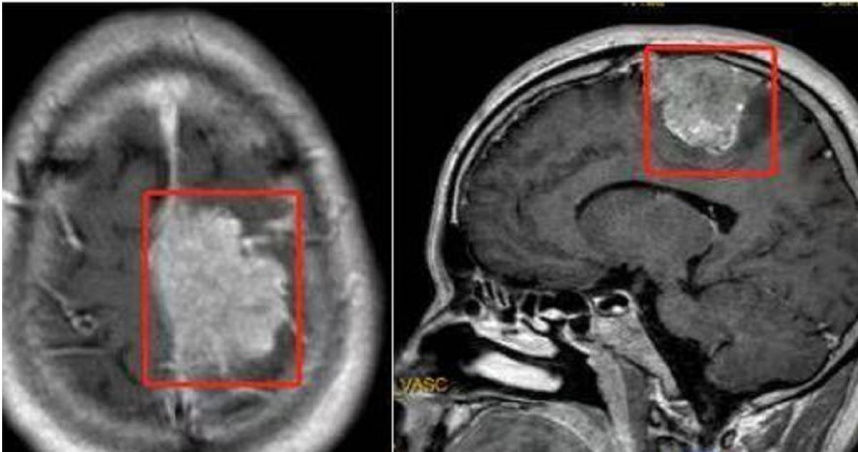

王某在醫院做頭顱磁振造影後,發現他的頭長了個矢狀竇旁腦膜瘤,且這個腫瘤直徑達到5.6公分,他之所以走路會「掉鞋」就是因為腫瘤壓迫到了神經,導致肢體偏癱、感覺障礙。人民醫院神經外科主任告訴他,只能手術切除,術後王某恢復良好,目前已痊癒出院。